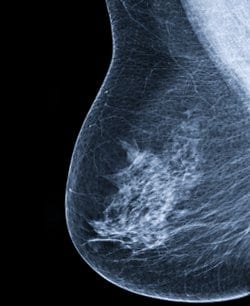

Atypical Hyperplasia קשורה עם סיכון גבוה לסרטן שד מאוחר

עם היפרפלזיה א-טיפית של השד מציגות סיכון אבסולוטי ללקות בסרטן שד של כמעט 30% לאחר 25 שנים, כך על פי דיווח מיוחד שפורסם ב- England Journal of Medicine.

החוקרים ציינו: “שיעור ההיארעות הכללי הגבוה אינו מקבל לרוב את תשומת הלב הראויה, ולכן, עם atypical hyperplasia אינן נכללות במרבית ההנחיות הנוגעות לקבוצות המצויות בסיכון גבוה.”

Atypical hyperplasia, הנחשבת כנגע שפיר, נמצאת בכ- 10% מהביופסיות הנלקחות מהשד, והכותבים מדגישים את חשיבות ההסרה הכירורגית של הנגע לאחר האבחנה.

מודלים נפוצים לניבוי הסיכון אינם מספקים הערכת סיכון אמינה בקרב הנשים הללו, ולכן, על המטפלים להשתמש בסיכון האבסולוטי על מנת להסביר לנשים את הסיכון להיארעות . יתר על כן, יש לשקול ביצוע של בדיקת MRI כבדיקת סקר נוספת לבדיקת הממוגרפיה.